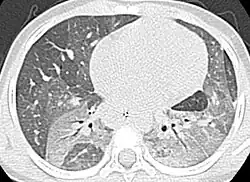

| Chest computerized tomography scan showing diffuse ground-glass opacities with air-bronchograms in the upper lobes and the left lower lobe. | |

Thoracic high-resolution computed tomography (HRCT) often shows signs of DIP,[17] however, HRCT has only been reported on in one study. HRCT shows a ground-glass appearance.[20]